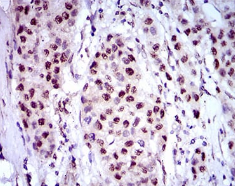

NAPSA Mouse Monoclonal antibody[10C4B]

The activation peptides of aspartic proteinases plays role as inhibitors of the active site. These peptide segments, or pro-parts, are deemed important for correct folding, targeting, and control of the activation of aspartic proteinase zymogens. The pronapsin A gene is expressed predominantly in lung and kidney. Its translation product is predicted to be a fully functional, glycosylated aspartic proteinase precursor containing an RGD motif and an additional 18 residues at its C-terminus.

Immunogen:    Purified recombinant fragment of human NAPSA (AA: 20-158) expressed in E. Coli.

IHC    1/200 - 1/1000